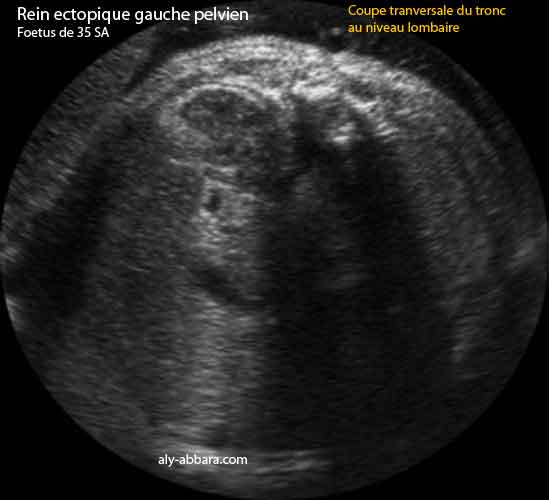

Rein gauche ectopique pelvien

Fœtus âgé de 35 SA

Trois images échographiques montrant d'abord l'absence de structures rénales dans la loge rénale lombaire classique gauche, puis le Doppler couleur met en évidence de la présence des deux branches artérielles rénales habituelles, mais celle de gauche se dirige vers le bas, ce qui peut évoquer la présence plus bas du rein gauche ; enfin, sur la coupe transverse - oblique du tronc au niveau de la région lombaire et pelvienne, on trouve le rein gauche en position ectopique médiane et directement derrière la vessie.